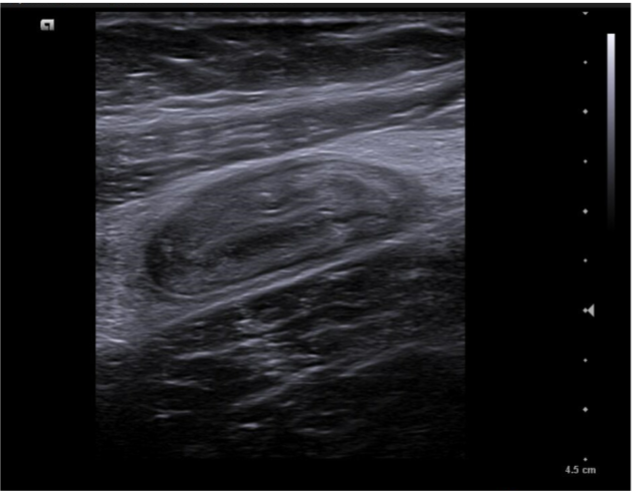

Caso 2. Asa intestinal fija con edema de pared por posible apendicitis o ileitis. Corte transversal con signo del donut.